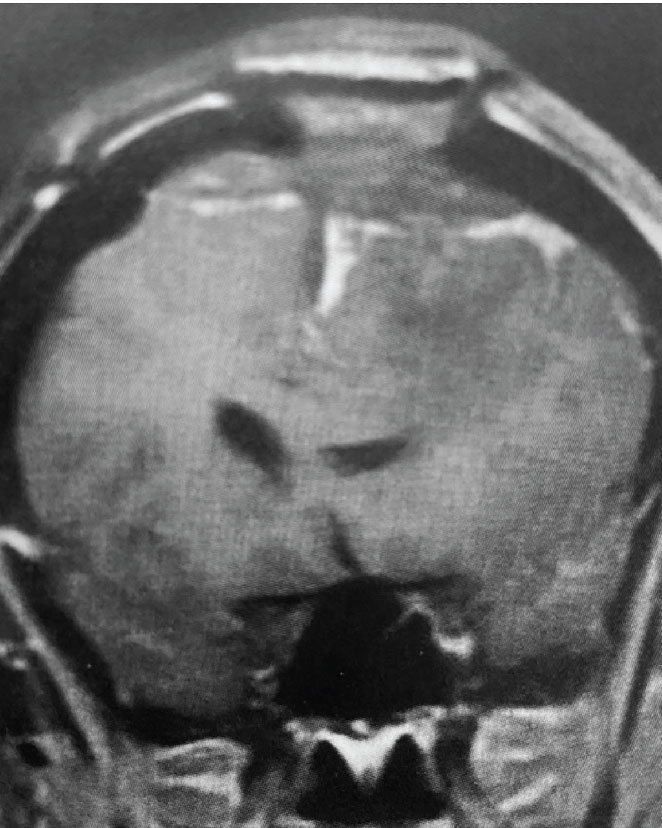

Fig 2. A) Post-operative, post-contrast, sagittal MRI.

Treatment: Given the size and location of this tumor, the best treatment was surgical removal. Surgery was performed by Dr. Michael Brisman. A craniotomy exposed the tumor along the convexity as well as the superior sagittal sinus. The tumor was removed, as was the involved convexity dura and the affected segment of the sagittal sinus. Removed dura and skull were replaced with duraplasty (with artificial dura) and a titanium mesh cranioplasty.

Outcome: The patient did very well and made a full recovery.